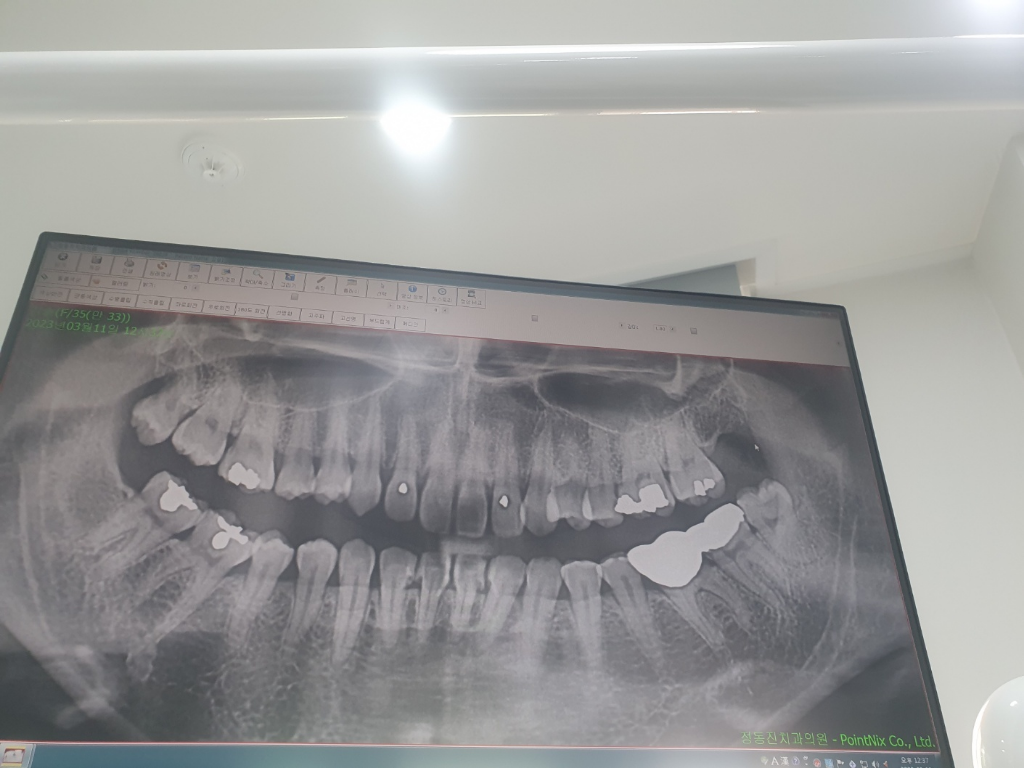

• 1번 째 사진

아말감 수복물이 깨졌을 수 있습니다 특히 왼쪽 위 치아 첫번째 큰 어금니 수복물은 사진상으로도 굉장히 충치가 컸고 처음부터 신경치료 가능성이 있었습니다 불편한 증상이 지속되면 신경치료 가능성도 있습니다